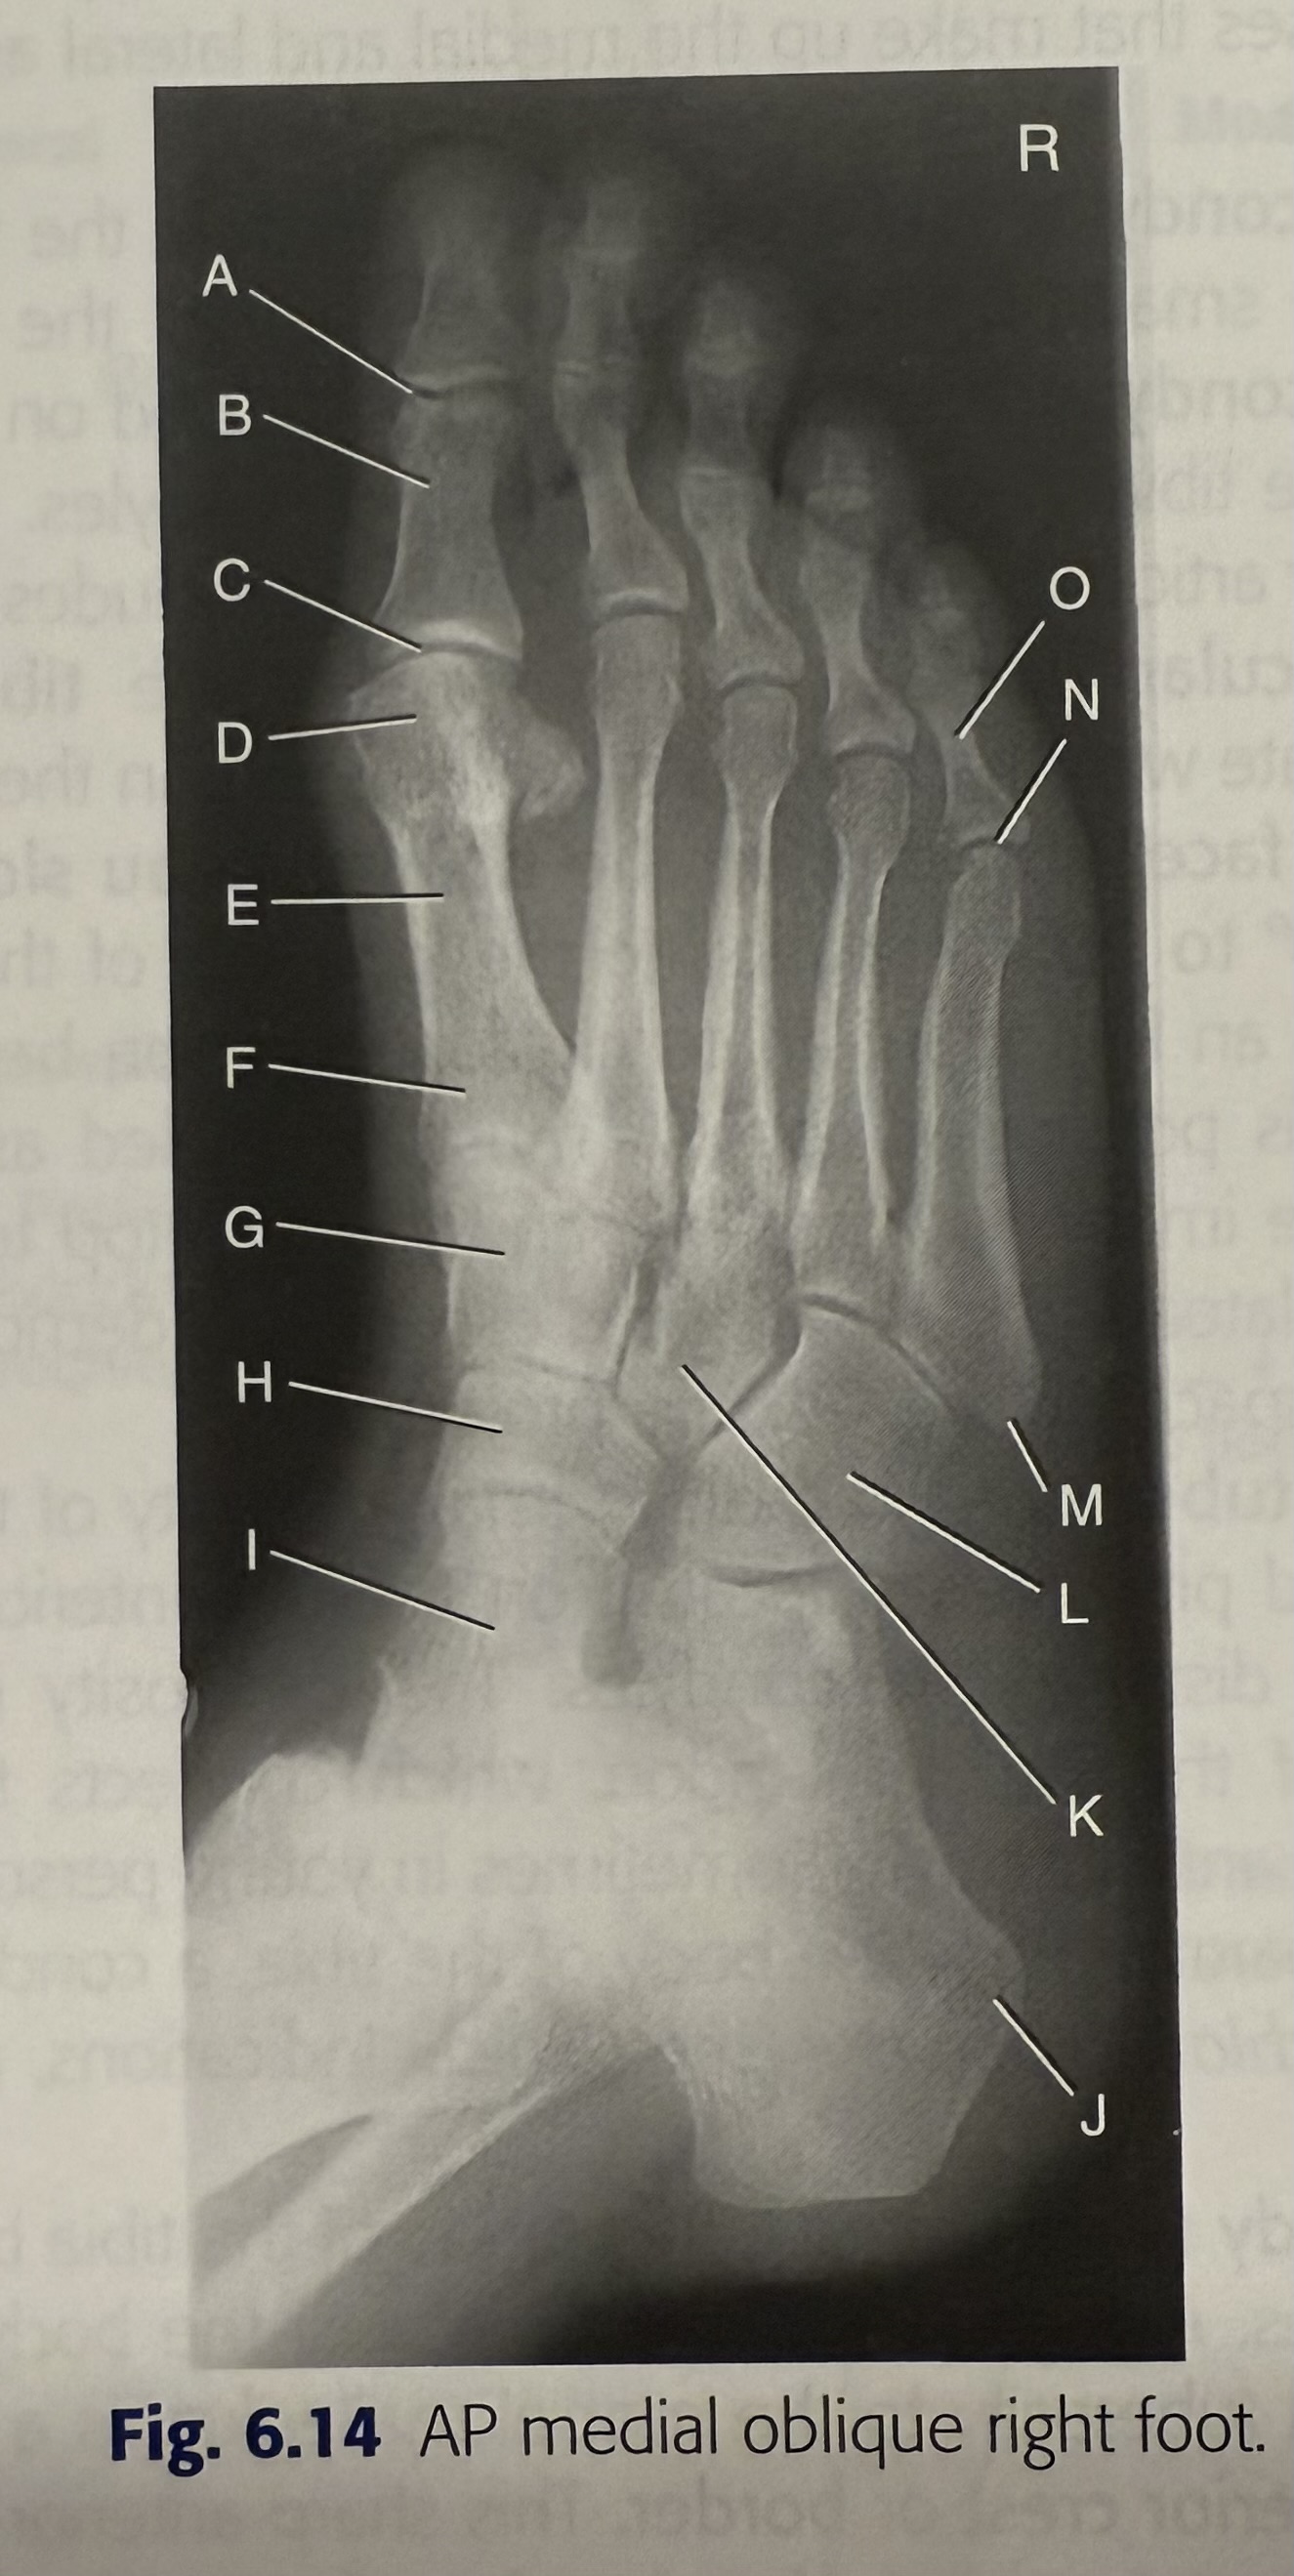

<p>A</p>

A

phalanges

New cards

<p>B</p>

B

77

<p>C</p>

tarsals

78

D

distal phalanx

79

<p>E</p>

E

middle phalanx

<p>F</p>

F

81

<p>G</p>

G

head

<p>H</p>

H

83

<p>I</p>

I

base

<p>J</p>

J

85